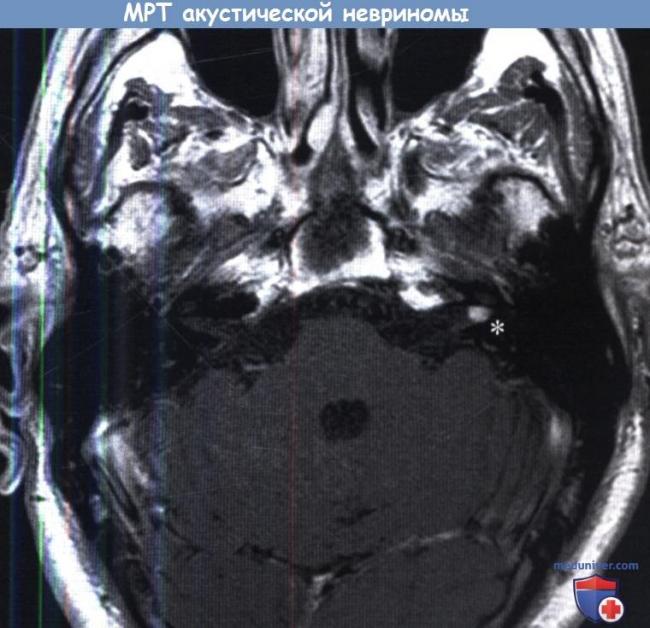

- Магнитно-резонансная томография косточек и связочного аппарата органов слуха, головного мозга.

Хирургическое лечение этого заболевания чаще всего проводится с целью осуществления кохлеарной имплантации, удаления гематомы, опухоли головного мозга или невриномы слухового нерва. Оперативное вмешательство также требуется в случае непрекращающегося мучительного шума в ушах или постоянно повторяющихся приступах сильного головокружения.

При подозрении на растущую в височной области опухоль, пациента направляют на компьютерную томографию. Еще один уточняющий причину метод диагностики – это УЗИ сосудов вертебробазилярного бассейна.